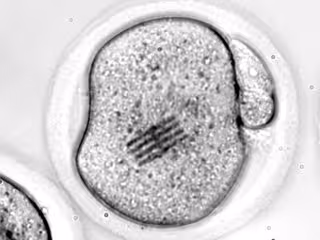

Embrión con un chip en su citoplasma

Embrión con un chip en su citoplasma - REMITIDA UGR - Archivo